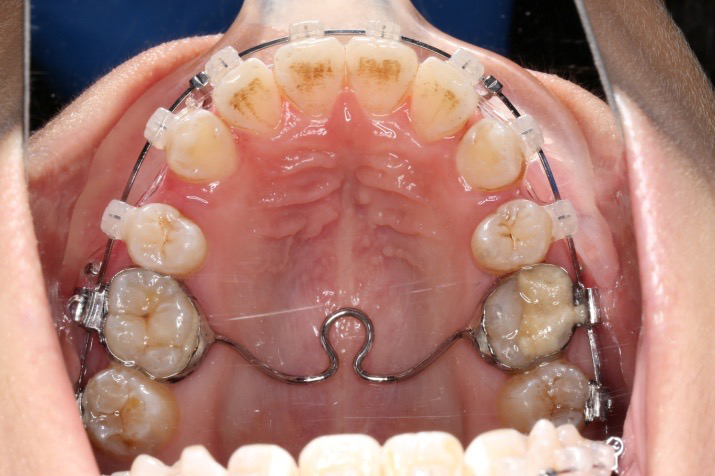

1拔牙矫治,拔除14、24、34、44,上颌TPA+上颌高位支抗钉内收前牙及压低前牙,改善侧貌突度及露龈笑

2通过合平面控制,实现下颌逆时针旋转,协调侧貌3前牙托槽定位以恢复患者微笑弧线为参考,改善笑弧笑线

拔除14、24、34、44,上颌TPA+上颌高位支抗钉

2.第2.5个月:2017.1.13 ◆ 上颌加TPA,植入1312-08种植钉,上下0.16cu-niti

上颌矫治的生物力学

上颌使用高位种植钉及长牵引钩,配合尖牙近远中的v-bend,上颌前牙的牙齿移动方式是整体往上,往后内收。

上后牙:高度保持不变/压入性移动,尽量避免伸长;▲垂直向控制中,应防止上后牙颊侧倾斜(TPA);▲腭尖高度控制也重要。